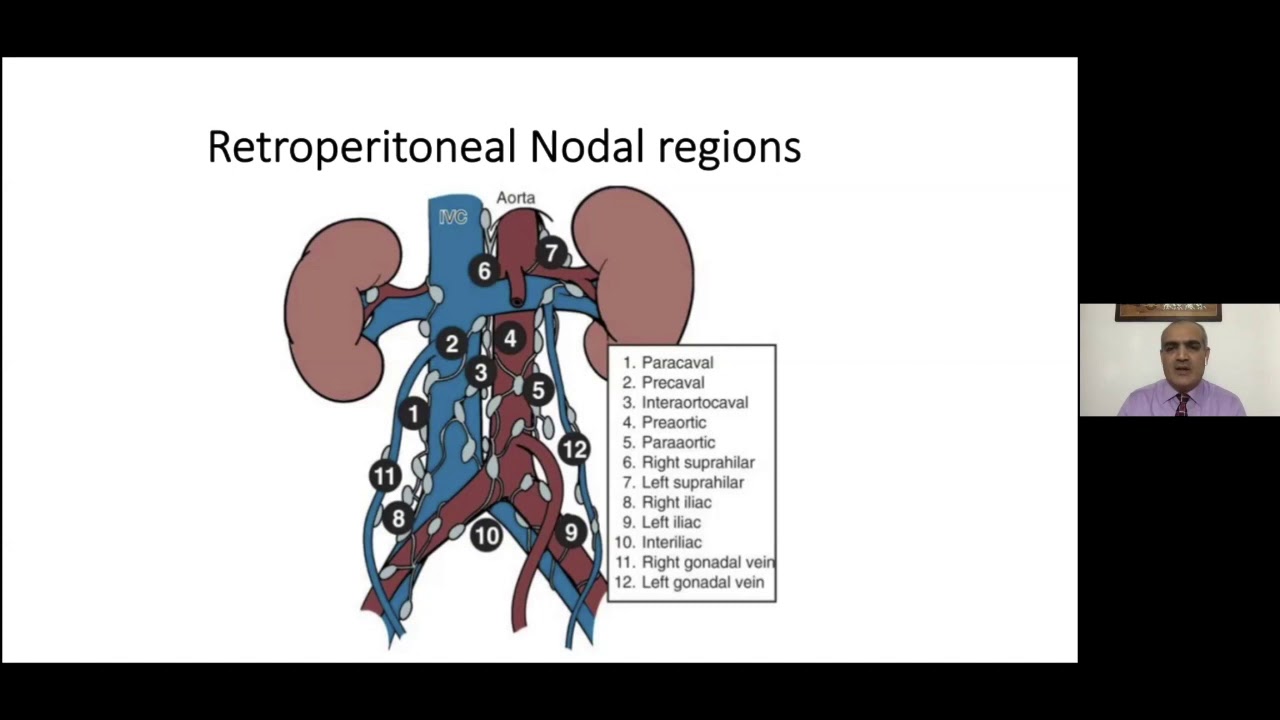

Robotic RPLND for Post Chemotherapy NSGCT

Oncology, Robotics ';